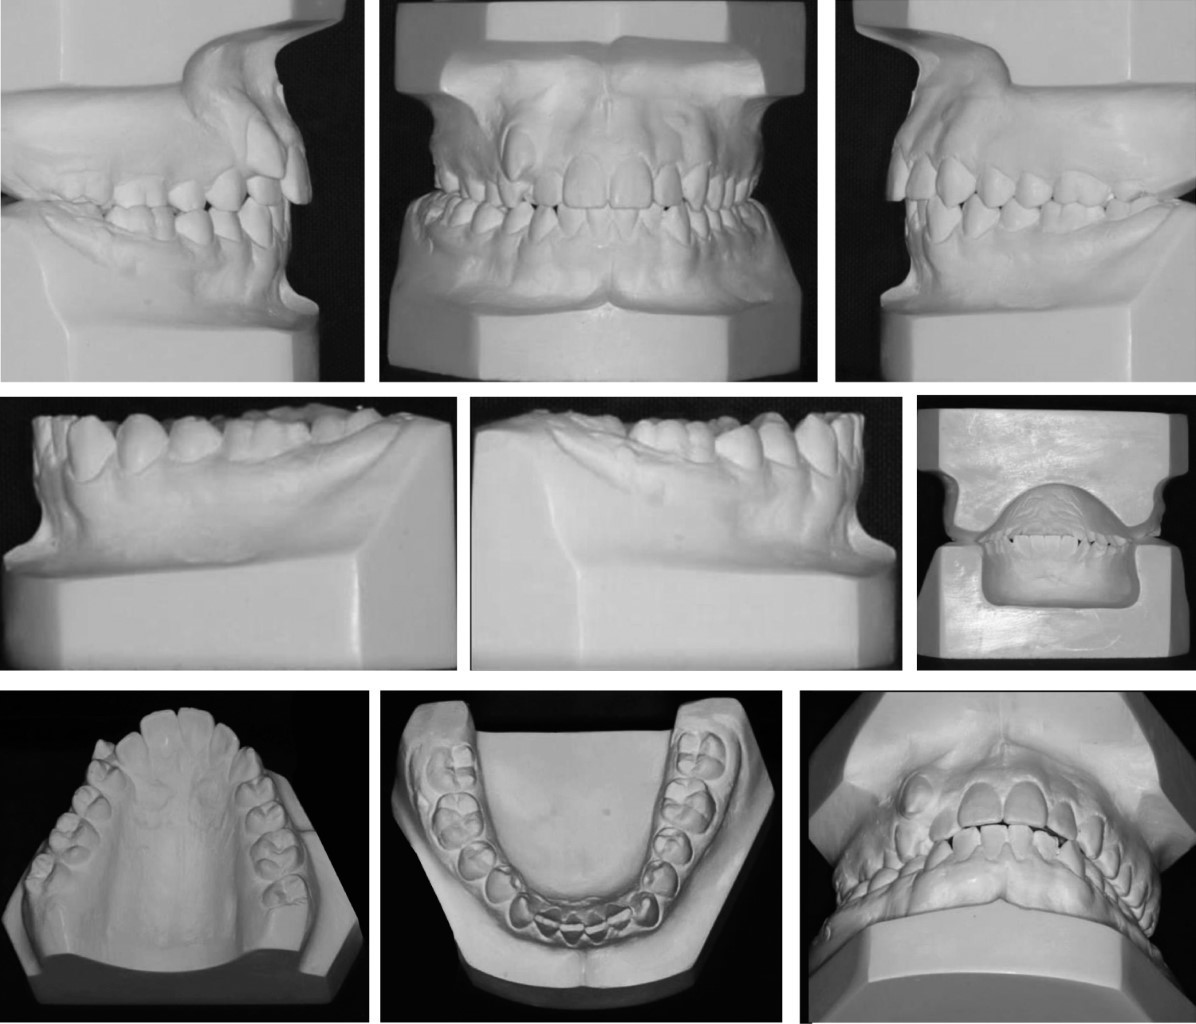

Paciente de género masculino de 13 años 10 meses de edad, sin antecedentes médicos relevantes, que acudió a la clínica de ortodoncia con motivo de consulta "quiero acomodar mi diente". En el análisis extraoral, el paciente presentó un perfil recto, biotipo dolicofacial incipiente, tercio inferior aumentado, pómulos sin proyección (Figura 1A). En la exploración intraoral el paciente mostró dentición permanente, clase II molar derecha, clase II canina derecha y clase I izquierda, forma de arco superior e inferior triangular, dientes grandes y cuadrados, línea media superior desviada 2 mm a la derecha, sobremordida horizontal 3 mm, sobremordida vertical 2 mm (Figura 1B). En el análisis de modelos en el estudio de Bolton presentó exceso maxilar de 3.2 mm, discrepancia de longitud de arco -6 mm superior y -2 mm inferior, con apiñamiento severo anterior superior (Figura 2).

Radiográficamente, en la ortopantomografía se observaron ramas mandibulares simétricas, cóndilos simétricos, niveles de crestas óseas sanas, presencia de gérmenes dentarios de terceros molares en los cuatro cuadrantes, proporción corona-raíz con relación de 1:1 y raíces cónicas (Figura 3A). En la radiografía lateral de cráneo se trazó la cefalometría de Steiner con el software Dolphin Imaging (9.0.00.19©1998-2004 Patterson Companies, Inc.), donde se observó una clase I esqueletal, vías aéreas superiores permeables, perfil recto e incisivos inferiores ligeramente retroinclinados (Figura 3B y Tabla 1).